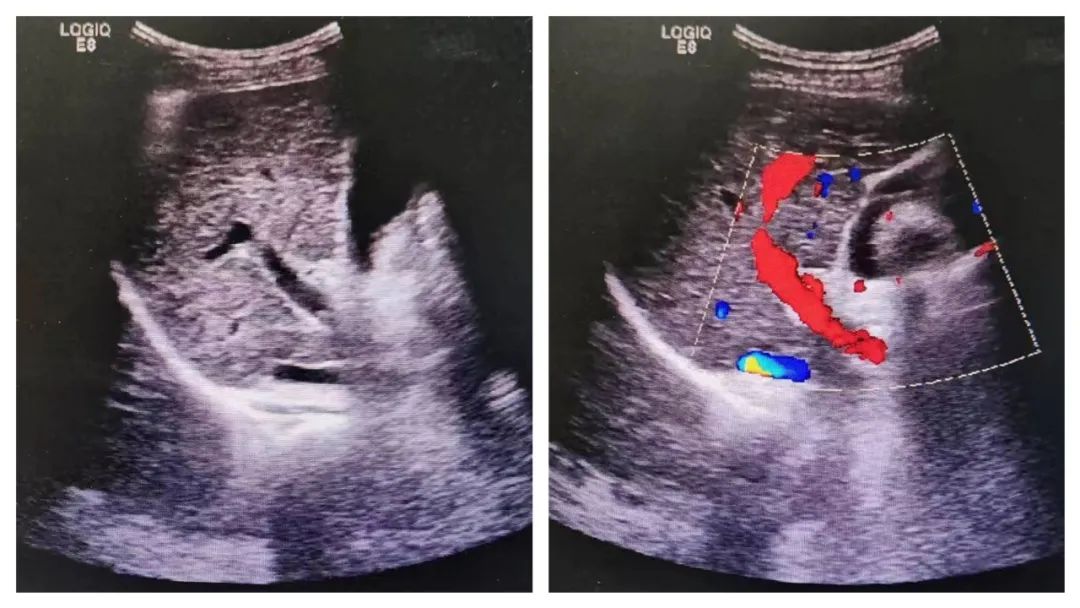

彩超,是利用多普勒效应原理在二维超声基础上加入彩色信号,来显示脏器内不同点上的血流信息,而呈现红、蓝两色,并没有其他颜色。

彩超的图像不仅显示脏器结构的切面图像,还能运用多普勒的原理观察血管血流的情况,通过收集不同部位的血流信息,综合二维超声图像特点,来进一步判断脏器的病变性质及脏器的功能情况。

因此,在做彩超检查时,显示器上显示的多数是黑白的二维图像,在需要观察脏器血流情况、加上彩色多普勒时,才会在黑白图像上叠加彩色血流图像。 这样大家就明白了,彩超大部分图像仍是黑白图像,只有在检查血流信息时才呈彩*图色**像。

△左图为黑白B超显示肝脏的结构,右图加上彩色多普勒功能清晰显示肝脏血管分布